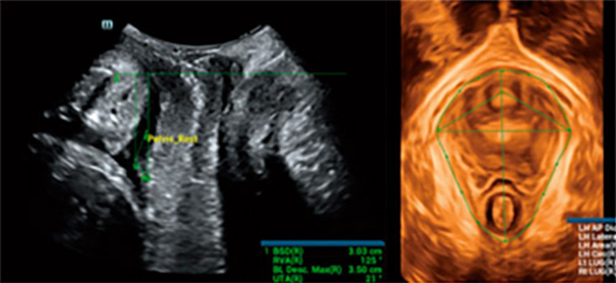

En el pasado, el tema de la salud del piso pĆ©lvico de las mujeres despuĆ©s del parto no despertĆ³ suficiente conciencia. Incluso, muchas personas creen errĆ³neamente que los trastornos del suelo pĆ©lvico (PFD), como el prolapso de Ć³rganos, la incontinencia urinaria y el dolor pĆ©lvico, son sĆndromes ānormalesā del parto o del envejecimiento. El diagnĆ³stico por ecografĆa ayuda a reconocer y evaluar con precisiĆ³n la salud del piso pĆ©lvico femenino.

La evaluaciĆ³n de la ubicaciĆ³n y la morfologĆa de todas las estructuras del tejido pĆ©lvico y el hiato del elevador son el enfoque principal en el examen del piso pĆ©lvico por ecografĆa. Sin embargo, la operaciĆ³n manual tradicional requiere mucho tiempo y depende del operador, y los ecografistas sin experiencia a menudo tienen dificultades en la localizaciĆ³n. Mientras tanto, un proceso de exploraciĆ³n ineficiente puede duplicar la incomodidad fĆsica y la vergĆ¼enza de las pacientes. Con el aumento de la concienciaciĆ³n sobre la salud del suelo pĆ©lvico de la mujer, es previsible que exista una demanda creciente de ecografĆas del suelo pĆ©lvico. Por lo tanto, es imperativo desarrollar un mĆ©todo de diagnĆ³stico del suelo pĆ©lvico por ecografĆa mĆ”s preciso, eficiente y fĆ”cil de usar.

Para ayudar a los ecografistas a obtener rĆ”pidamente secciones y medidas estandarizadas en exĆ”menes complejos del piso pĆ©lvico y mejorar la eficiencia del diagnĆ³stico, Mindray ha desarrollado Smart Pelvic, una soluciĆ³n de ecografĆa inteligente para el piso pĆ©lvico. Puede obtener automĆ”ticamente mediciones pĆ©lvicas completas y ofrecer imĆ”genes 3D automĆ”ticas del hiato del elevador, junto con medidas del diĆ”metro longitudinal, el diĆ”metro transversal, el Ć”rea del hiato del elevador y el tama?o del espacio del elevador de la uretra. Los ecografistas pueden obtener datos clĆnicos completos para una evaluaciĆ³n precisa en unas pocas interacciones simples que toman solo 1/3 del tiempo que consumen los exĆ”menes tradicionales. AdemĆ”s, Mindray ofrece tres estĆ”ndares industriales primarios que admiten diferentes tipos de sondas y posibilitan un uso estandarizado.

Smart Pelvic